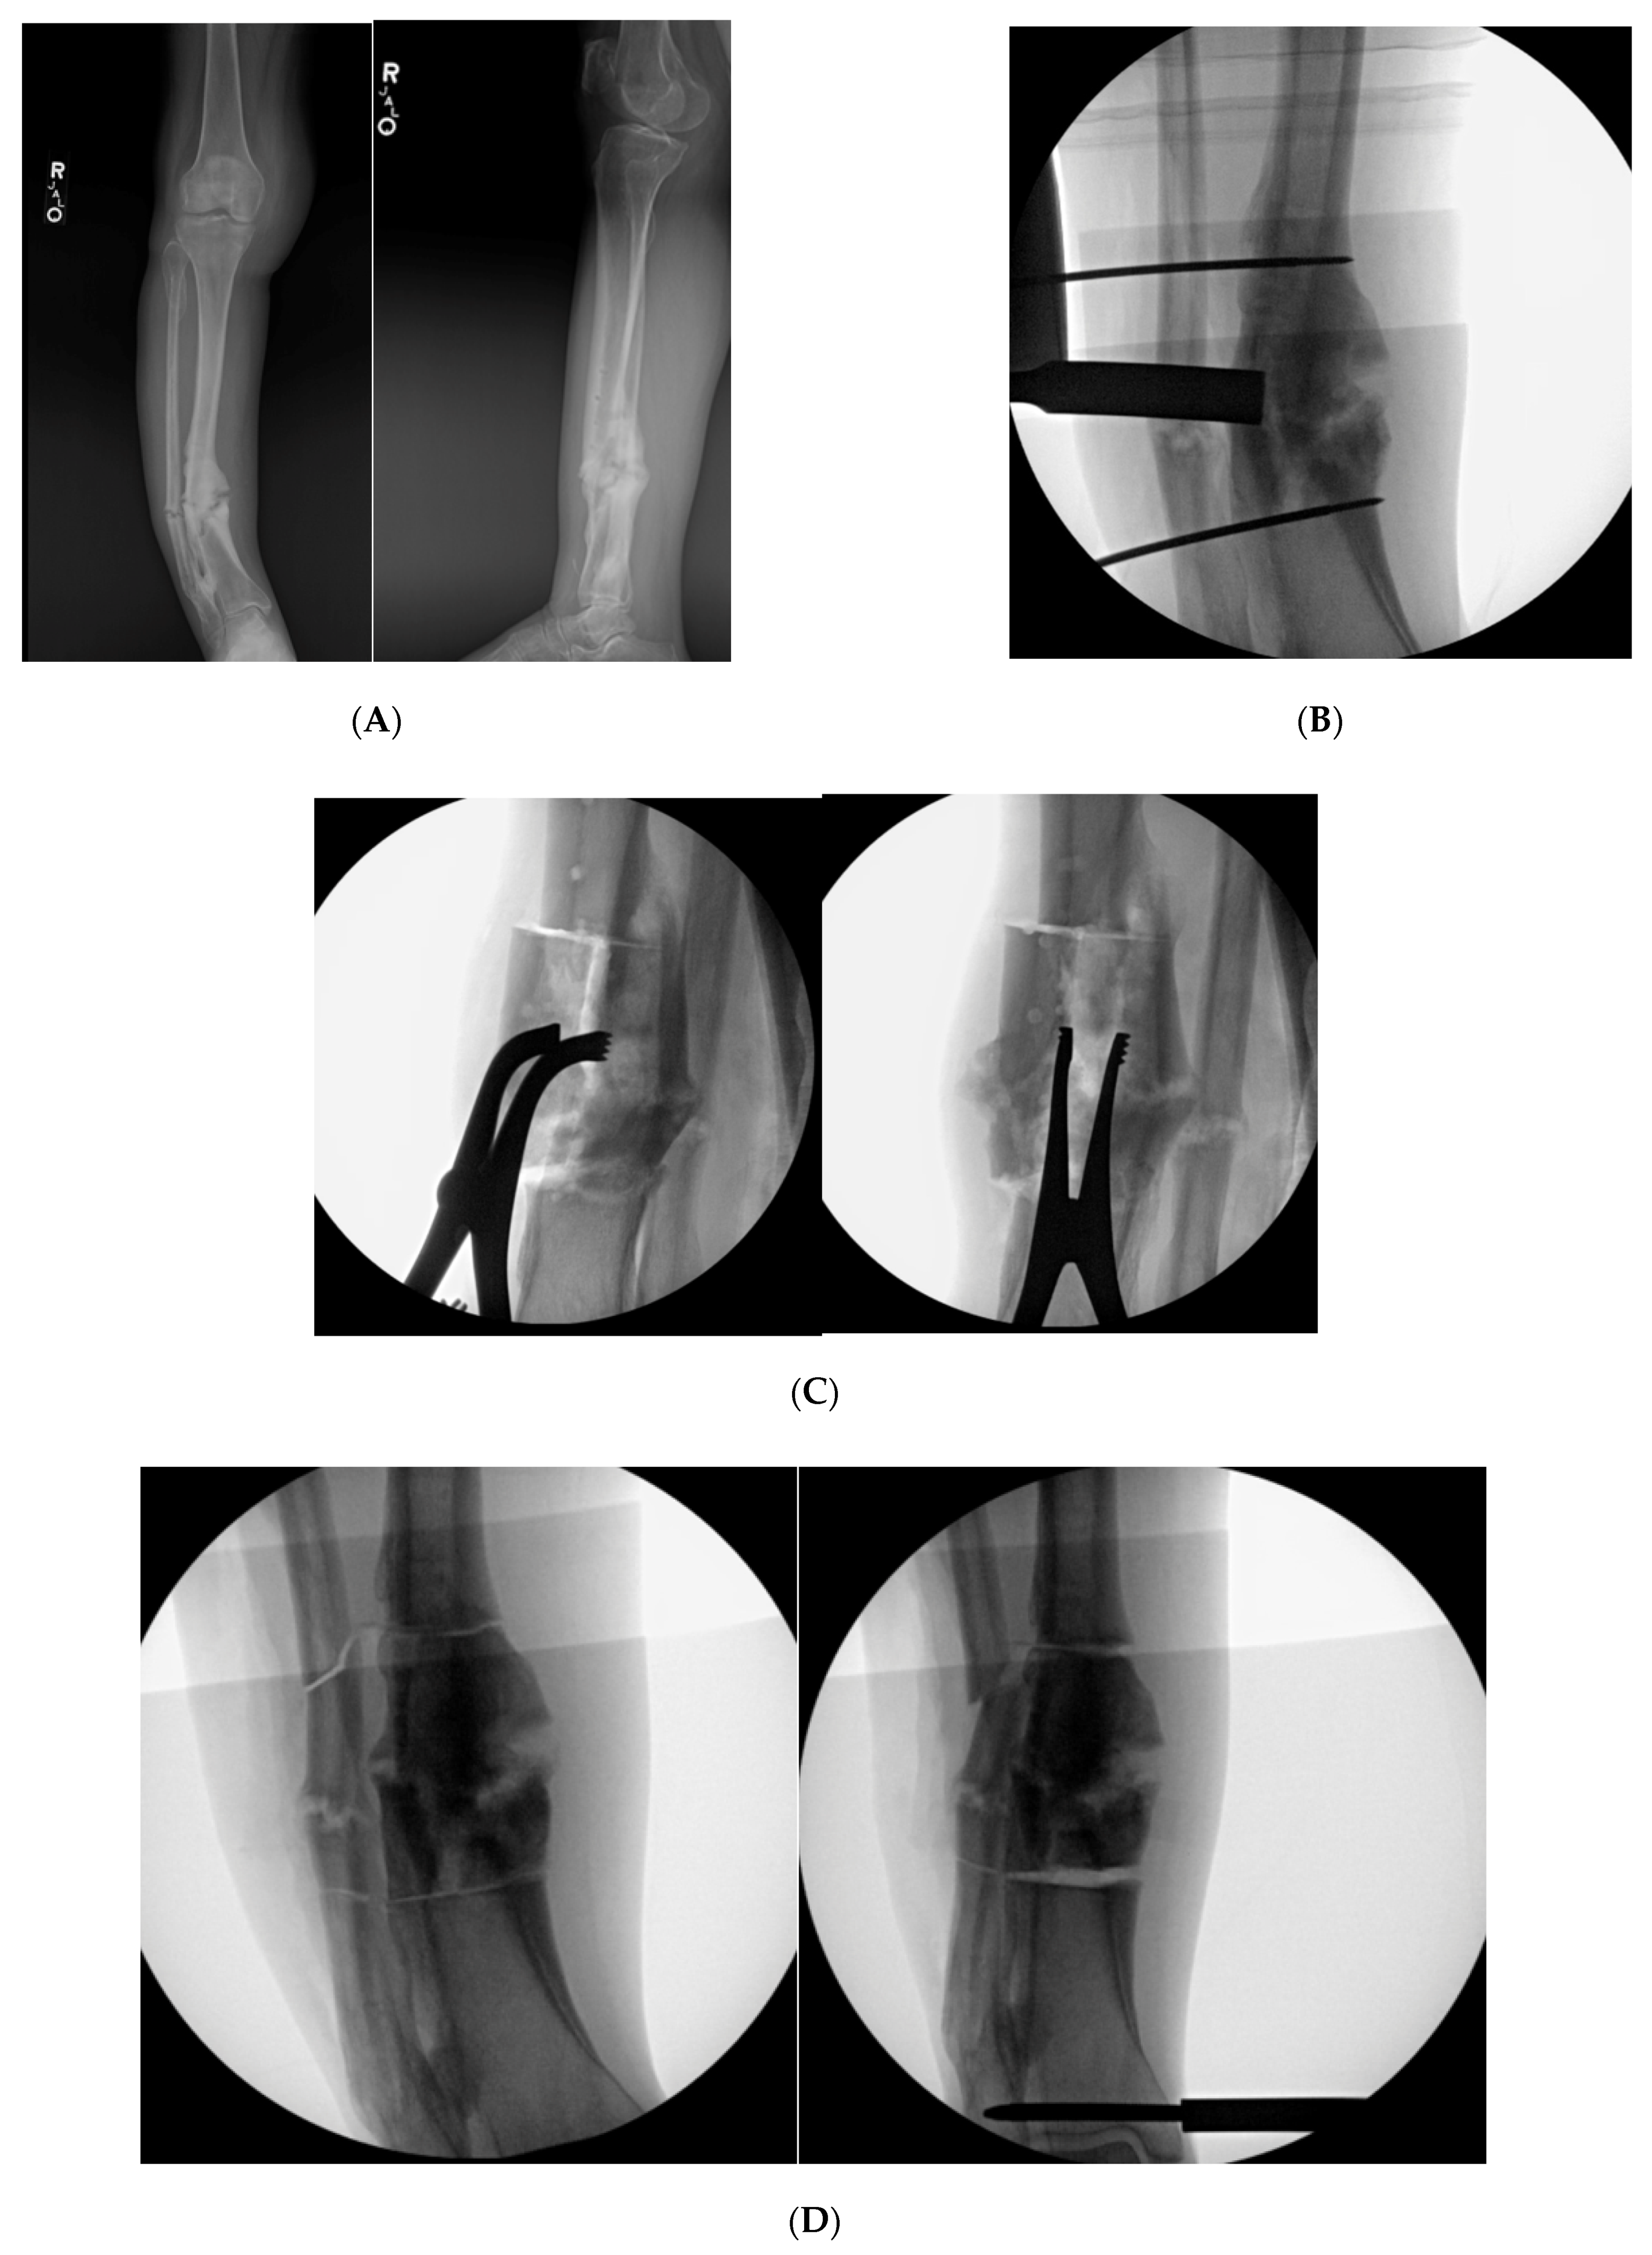

9.4. Case 4

Figure 7. (A): AP and lateral XR demonstration varus non-union deformity with segmental fibular fracture. (B): Intraoperative fluro view with threaded k-wire at proximal and distal aspect of malunited segment. A core reamer is being used to create the sequential bicortical drill holes. A core reamer can be used if the malunited segment is significantly larger than a 3.5 drill bit. (C): Note the lamina spreaders being utilized to open the osteotomized clamshell segment. (D): Medial universal distractor being utilized to assist with deformity correction. The distractor can be left in place during the nailing procedure. (E): AP and lateral 3-month postoperative radiographs demonstrating healed clamshell and fibular osteotomies.